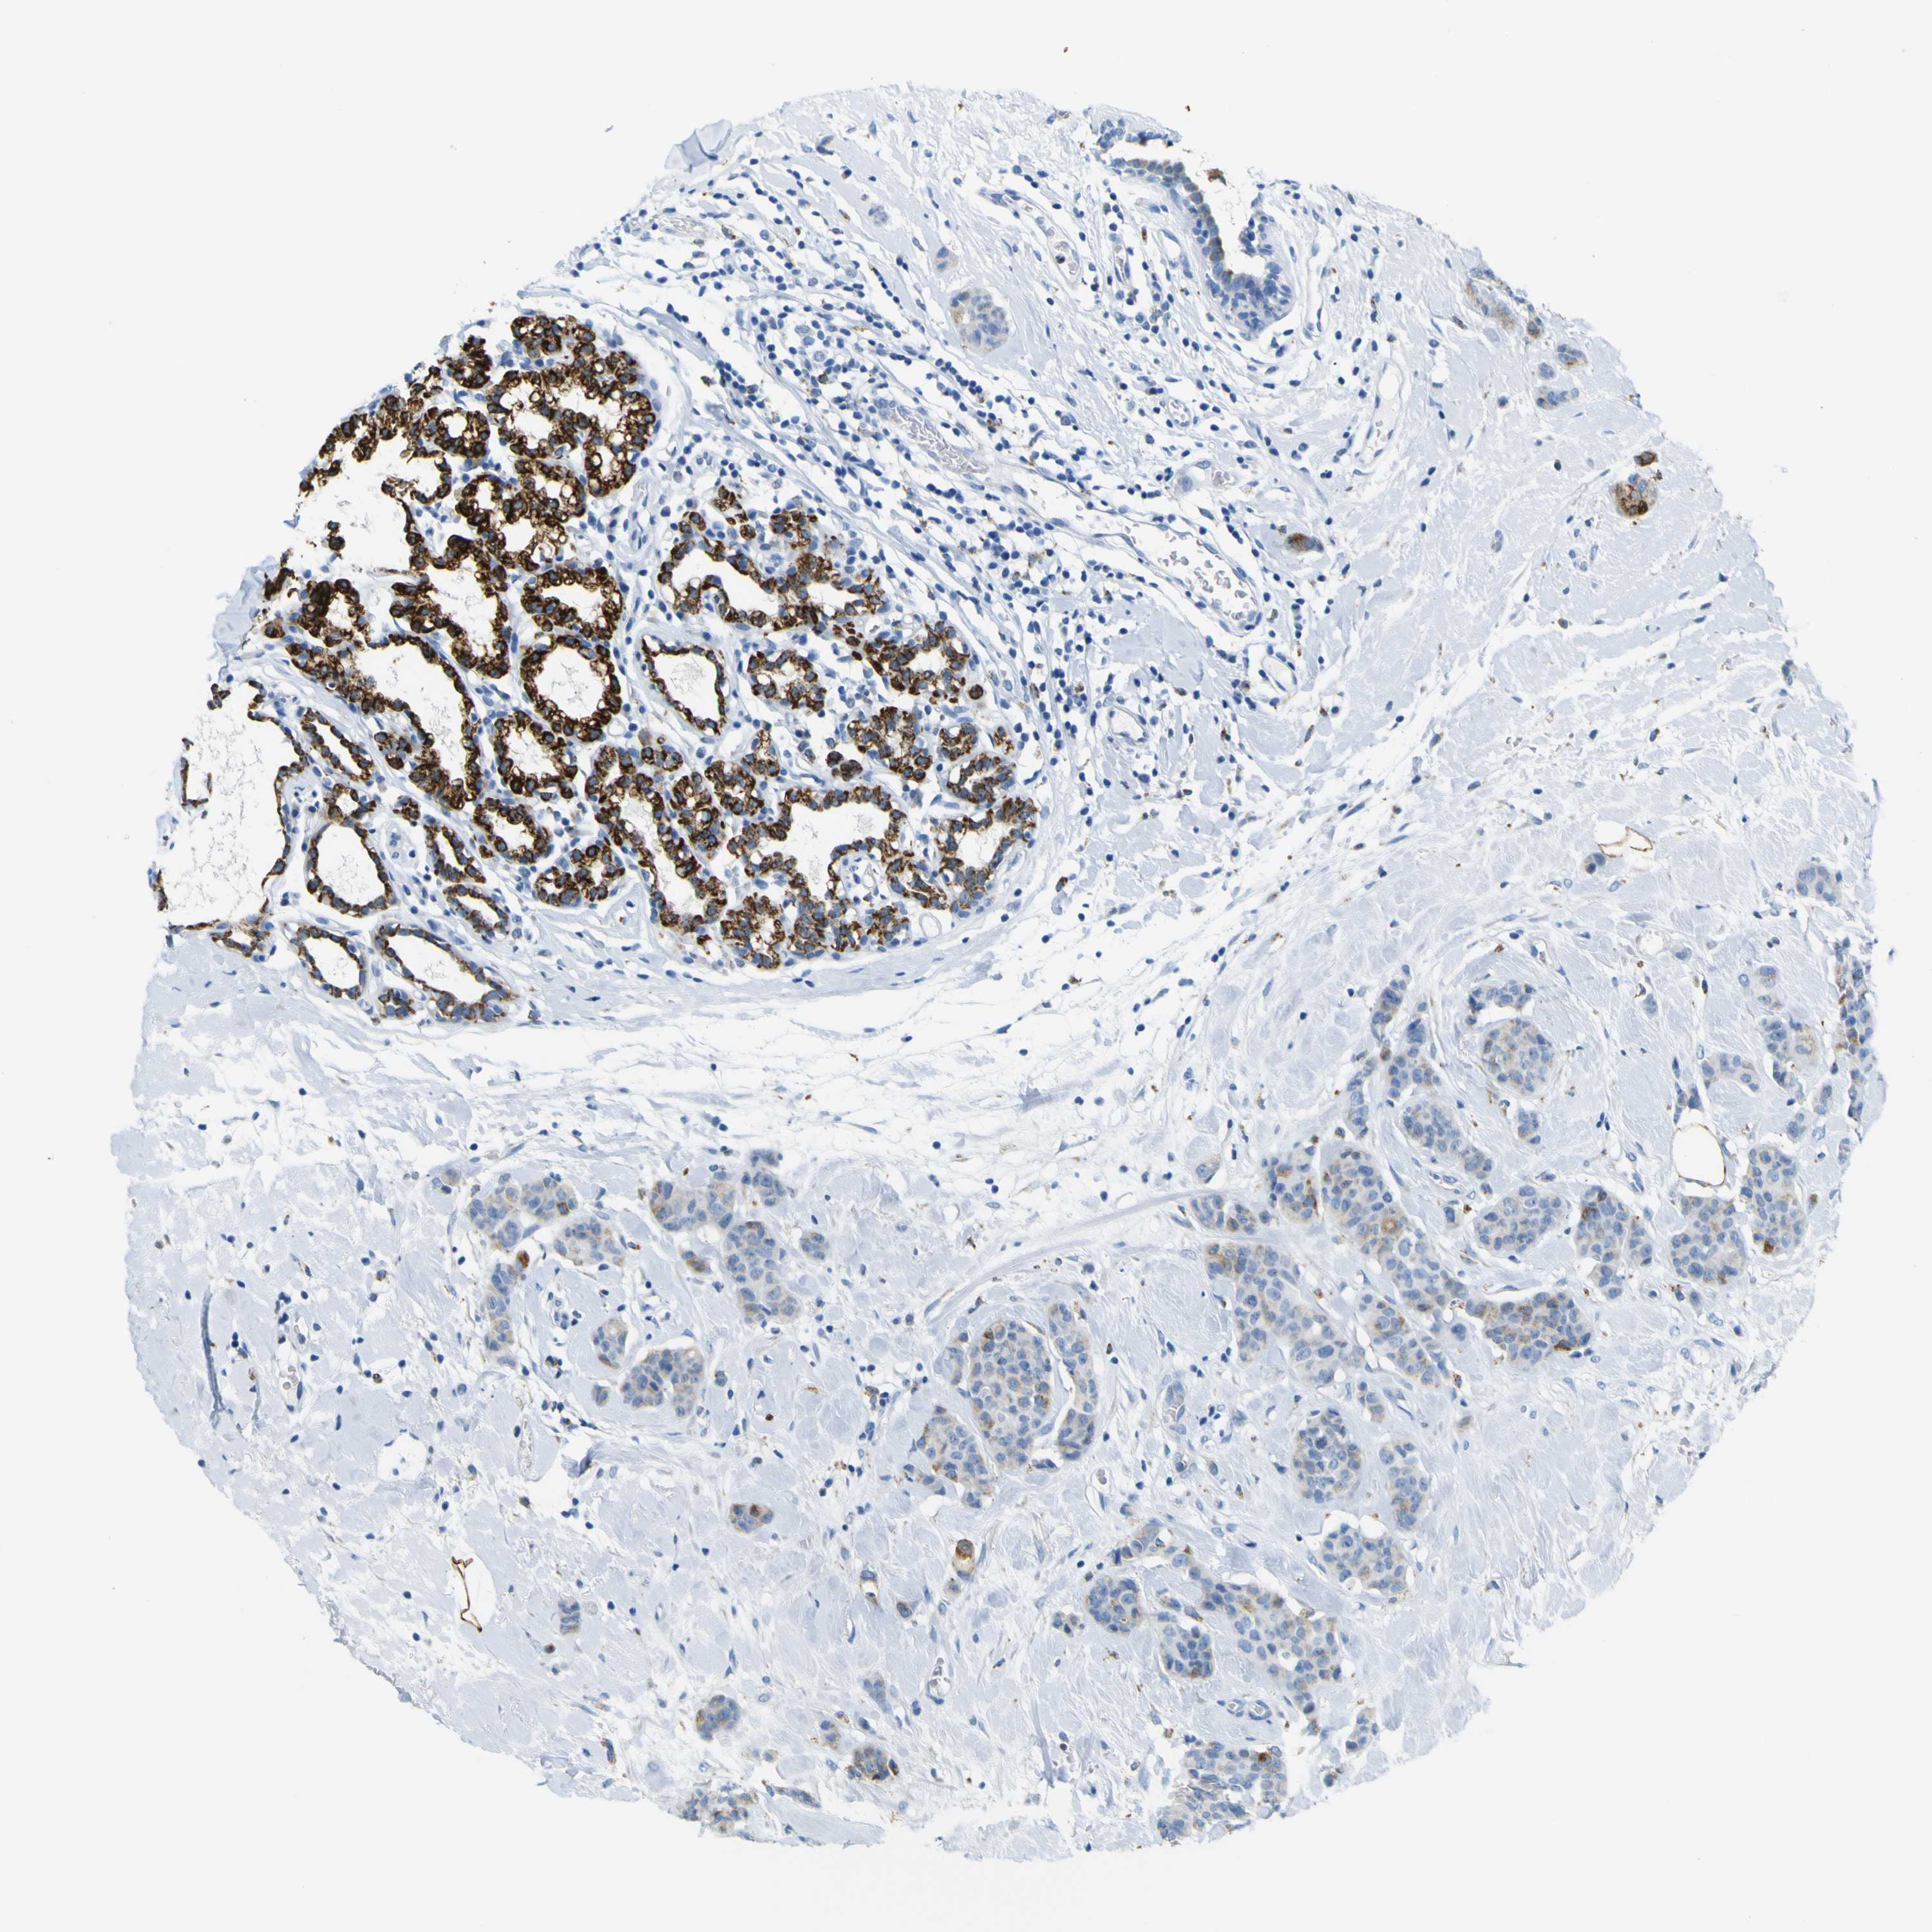

ACSL1

• ACSL1

CANCER BREAST CANCER Show tissue menu

BRCA TCGA BRCA VALIDATION PROTEIN EXPRESSION

Breast cancer

Human cancer